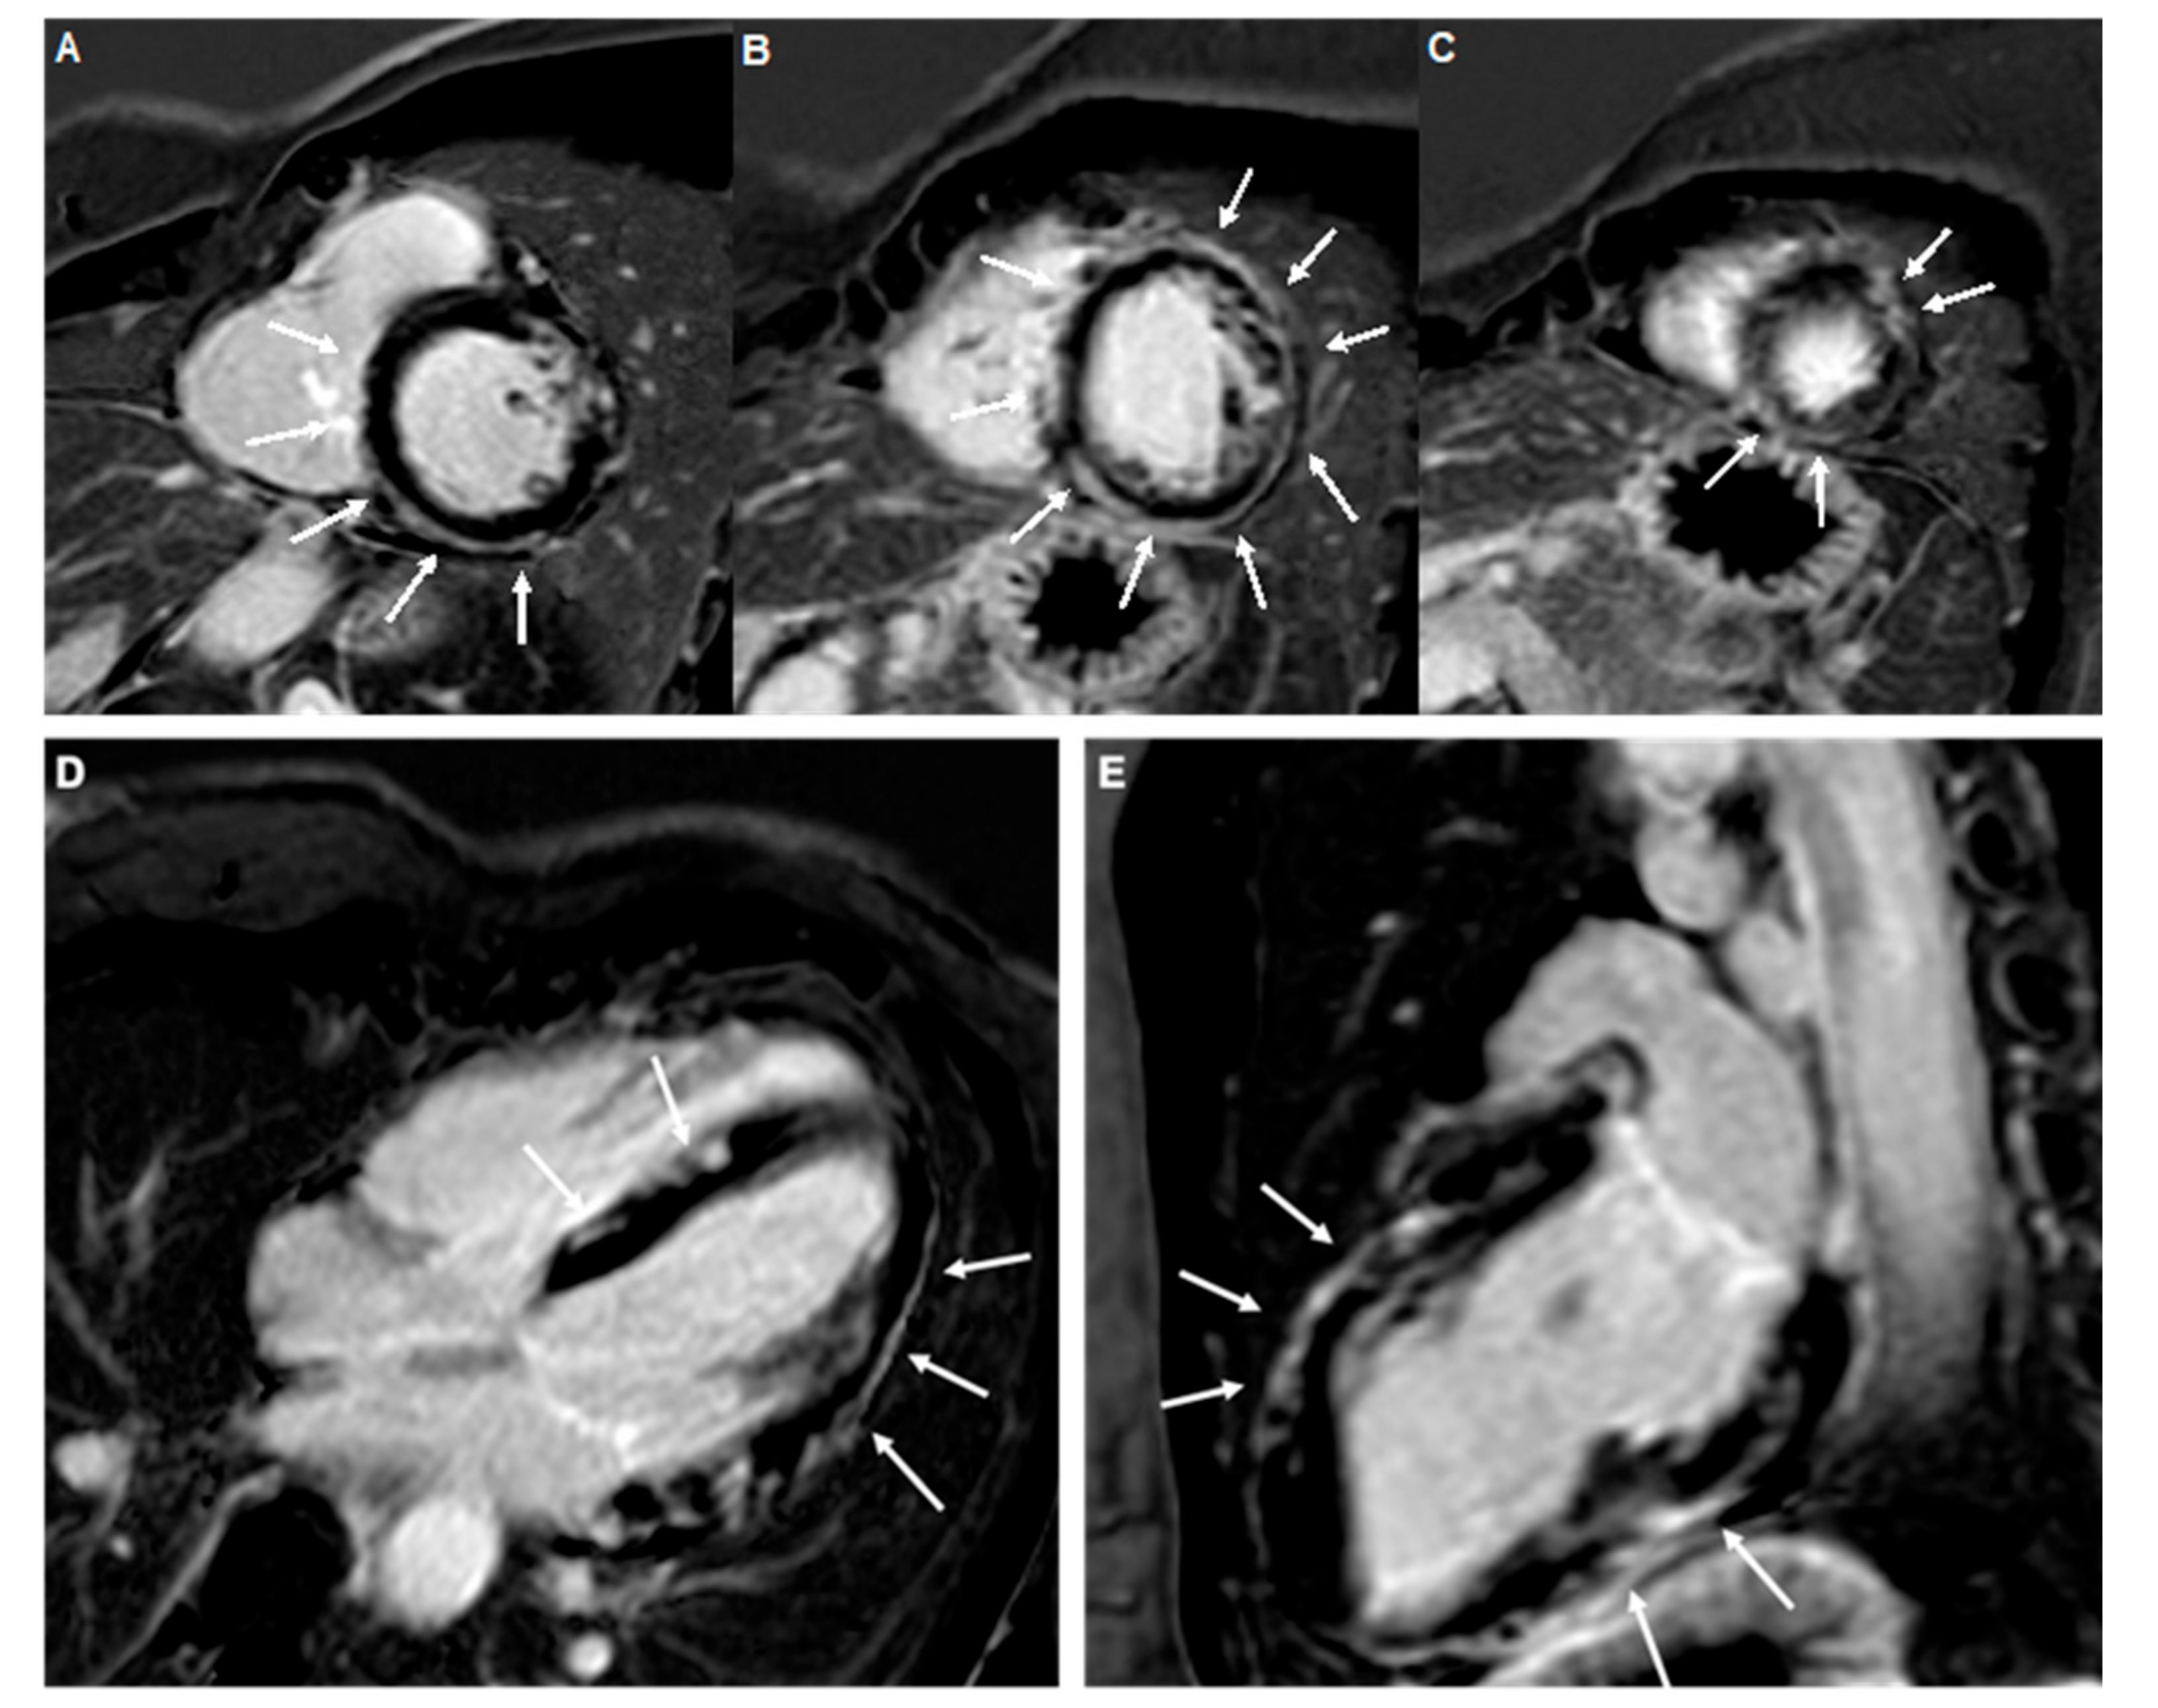

5.5. Cardiac Magnetic Resonance

- Ferreira, V.M.; Schulz-Menger, J.; Holmvang, G.; Kramer, C.M.; Carbone, I.; Sechtem, U.; Kindermann, I.; Gutberlet, M.; Cooper, L.T.; Liu, P.; et al. Cardiovascular Magnetic Resonance in Nonischemic Myocardial Inflammation. J. Am. Coll. Cardiol. 2018, 72, 3158–3176. [Google Scholar] [CrossRef] [PubMed]

- Zorzi, A.; Marra, M.P.; Rigato, I.; De Lazzari, M.; Susana, A.; Niero, A.; Pilichou, K.; Migliore, F.; Rizzo, S.; Giorgi, B.; et al. Nonischemic Left Ventricular Scar as a Substrate of Life-Threatening Ventricular Arrhythmias and Sudden Cardiac Death in Competitive Athletes. Circ. Arrhythmia Electrophysiol. 2016, 9, e004229. [Google Scholar] [CrossRef]